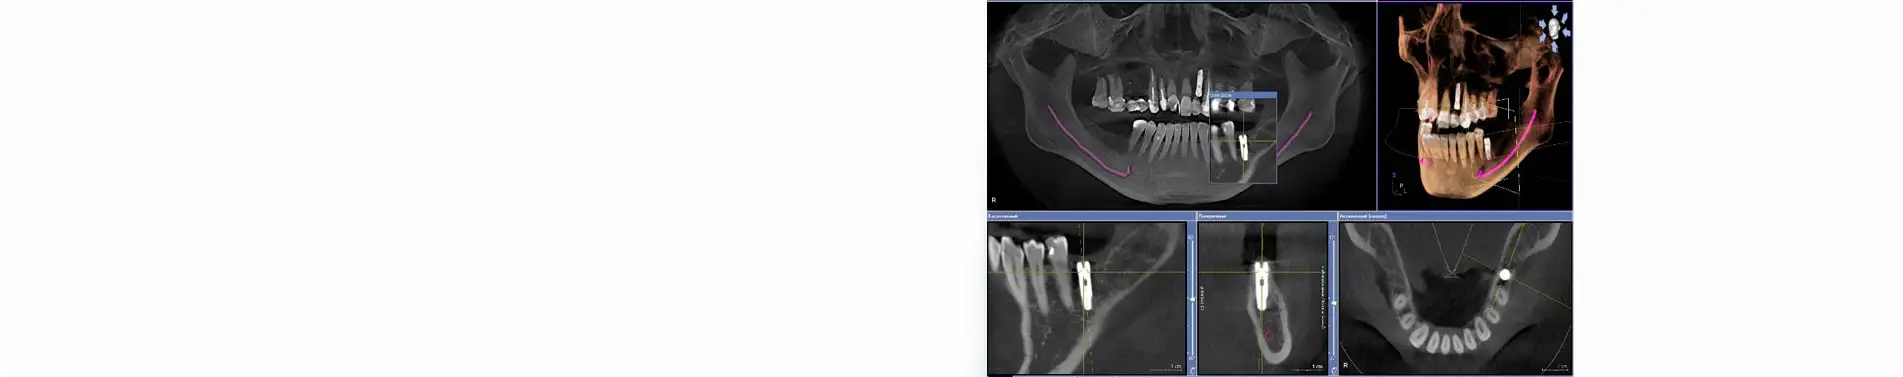

- сделать рентгенографическое 3D исследование для определения размера и местоположения имплантата.